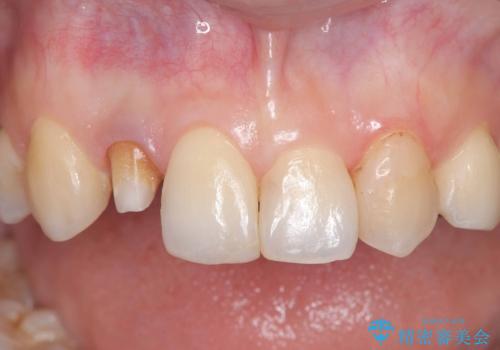

- 「前歯の見た目が気になる」を主訴に来院された患者様です。

失活歯による歯の変色とCR(コンポジットレジン)の劣化による審美不良でした。

オールセラミッククラウンで治療し見た目の改善を行いました。

まず劣化したCRと虫歯を除去した後、仮歯に置き換えました。歯のマージンラインを綺麗に削り光沢が出るまで研磨した後にオールセラミッククラウンの型取りを行っています。